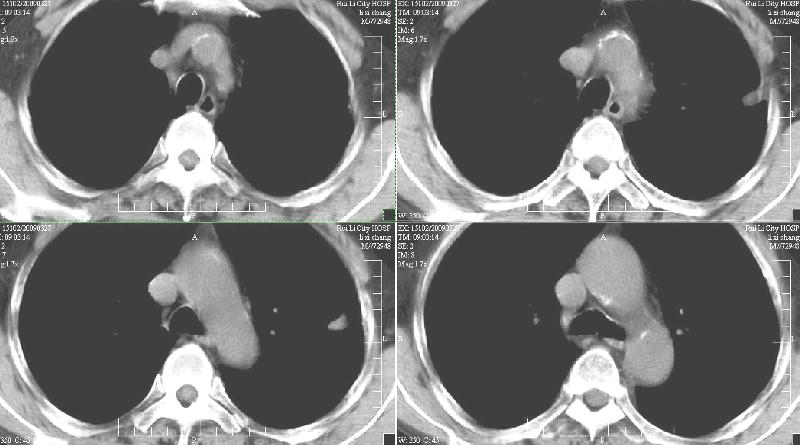

标题: CT19134:M,58岁。咳嗽痰多一月,不发热。 [打印本页]

标题: CT19134:M,58岁。咳嗽痰多一月,不发热。

ct:慢性支气管炎,(轻度泡性气肿),并左上叶尖后段结核球(可能大)。2、左下叶背段小片感染(考虑结核)